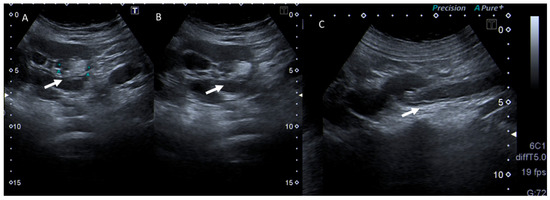

Background: Orthopedic trauma during pregnancy is a rare yet complex medical challenge, impacting both maternal and fetal health. Among these, femoral fractures are particularly uncommon but require careful management to minimize maternal and fetal risks. Methods: We report the case of a 28-year-old woman, gravida 4, para 3, at 40 weeks of gestation, who sustained a left mid-femoral diaphyseal fracture following a low-energy fall. A multidisciplinary team approach, including obstetric, orthopedic, anesthetic, and neonatal specialists, was employed. Preoperative imaging by X-ray was performed under lead-apron protection. The patient underwent an emergency C-section, followed by closed reduction and internal fixation with an intramedullary nail. Results: The surgical intervention was successful, with minimal radiation exposure. Postoperative management included thromboprophylaxis, calcium, vitamin D supplementation, and physiotherapy. The patient recovered well, achieving fracture healing within three months. Postpartum bone density assessment was recommended, suspecting pregnancy- and lactation-associated osteoporosis. Conclusions: Managing femoral fractures during pregnancy necessitates a balance between maternal and fetal well-being. A collaborative, multidisciplinary approach ensures optimal outcomes. Early surgical intervention, proper radiation precautions, and postpartum bone health assessment are crucial in these cases. Further research is needed to understand risk factors and preventive strategies for pregnancy-associated osteoporosis. Full article

Show Figures

Figure 1